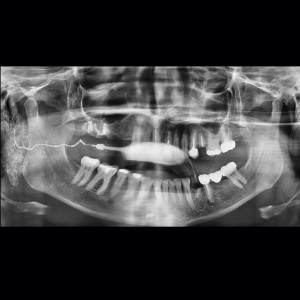

SERVICIOS 2D

SIALOGRAFIA

• Glándulas parótidas y sub maxilares